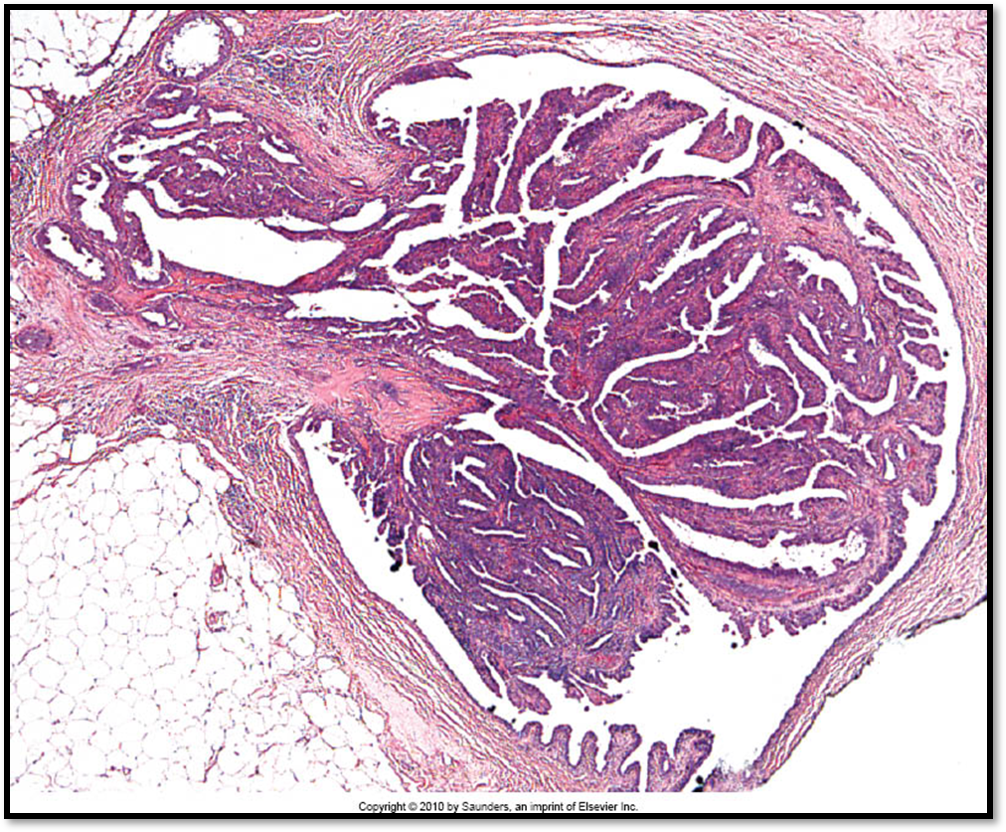

See attached image

Intraductal papilloma

Bloody nipple discharge